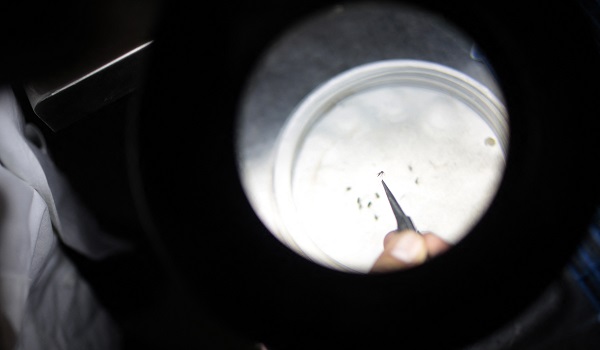

WASHINGTON, 10 November- Pentadbiran Makanan dan Ubat-ubatan (FDA) Amerika Syarikat meluluskan vaksin pertama di dunia untuk virus chikungunya iaitu penyakit bawaan nyamuk.

Chikungunya menyebabkan demam dan sakit sendi yang teruk, biasanya berlaku di kawasan tropika dan subtropika Afrika, Asia Tenggara serta sebahagian benua Amerika.

Chikungunya mula dikenal pasti di Tanzania pada 1952 dan kini telah direkodkan di lebih 110 negara, menurut Pertubuhan Kesihatan Sedunia (WHO). -AFP